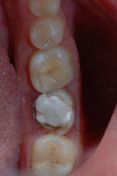

Situazione iniziale dove il 4.6 è già stato devitalizzato e ricostruito con perno in fibra mentre il 4.7 deve essere ancora trattato dal punto di vista endodontico.

Gli elementi 46 e 47 sono stati devitalizzati a causa di carie penetranti per questo si è reso necessario una ricopertura cuspidale degli elementi per proteggerli durante i carichi masticatori. Si è pertanto deciso di effettuare delle corone in ceramica integrale metal-free. L'altezza della corona clinica dei due molari è stata ritenuta insufficiente per una correta ritenzione del restauro definitivo per cui prima della terapia protesica definitiva è stato effettuato un intervento di allungamento di corona clinica. Si può notare la completa e corretta integrazione dei restauri protesici a distanza di 4 mesi dall'intervento e ad una settimana dalla cementazione definitiva. (Si ringrazia per la collaborazione il laboratorio Lunedei)